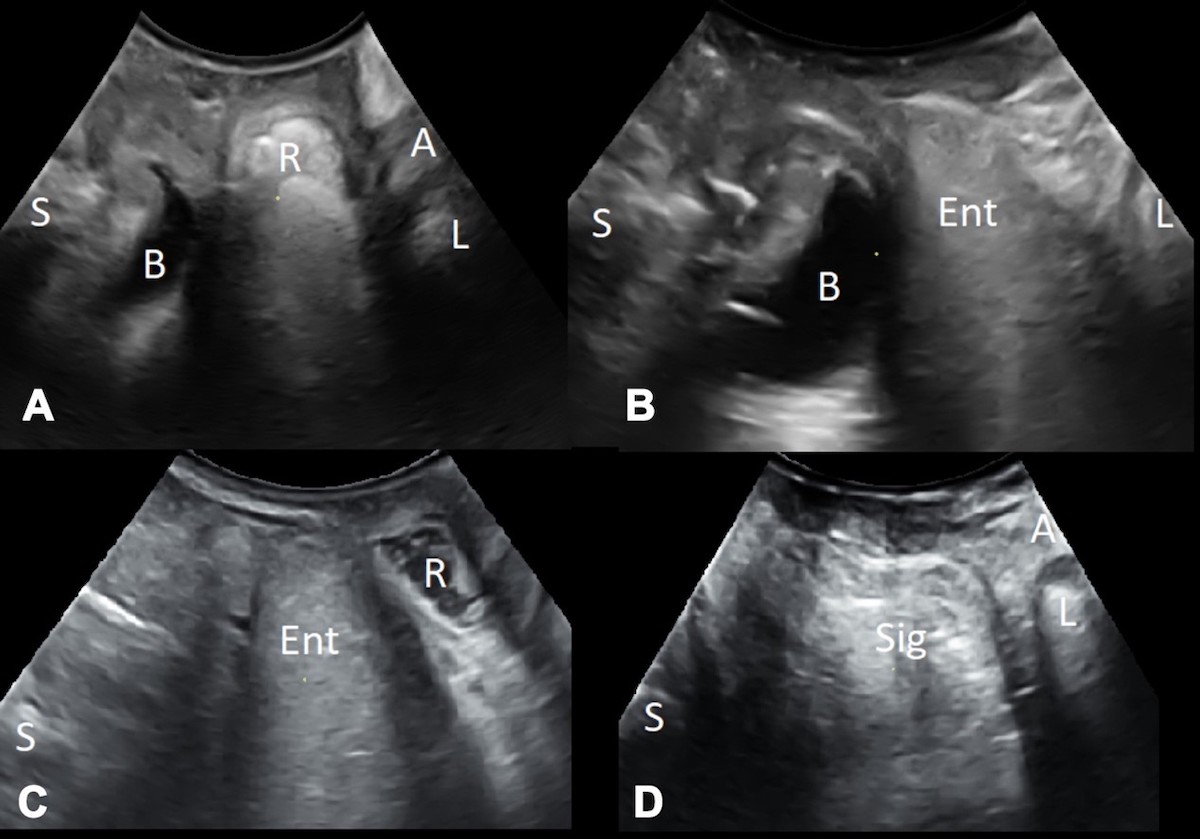

One of the main applications of translabial ultrasound is in the quantification of POP. There is a good correlation between ultrasound and clinical measurements of POP (Dietz et al 2016). Unlike clinical staging systems which are limited to describing surface anatomy, imaging provides information on underlying organs and functional anatomy. A clinical ‘cystocele’ may turn out to be a urethral diverticulum or a vaginal cyst. A clinical ‘rectocele’ may be due to five different anatomical conditions, namely perineal hypermobility, a true rectocele (where there is a diverticulum of the anterior rectal wall into the vagina through a rectovaginal septal defect), an enterocele, a rectoenterocele, or a rectal intussusception (Figure 1) (Dietz & Beer-Gabel 2012). Imaging is required to differentiate these conditions.

Figure 1: Mid sagittal view on Valsalva showing a rectocele (A), an enterocele (B), a rectoenterocele (C) and a rectal intussusception (D). S=symphysis pubis, B=bladder, R=rectocele, A=anal canal, L=levator ani muscle, E=enterocele, Sig=sigmoid colon.